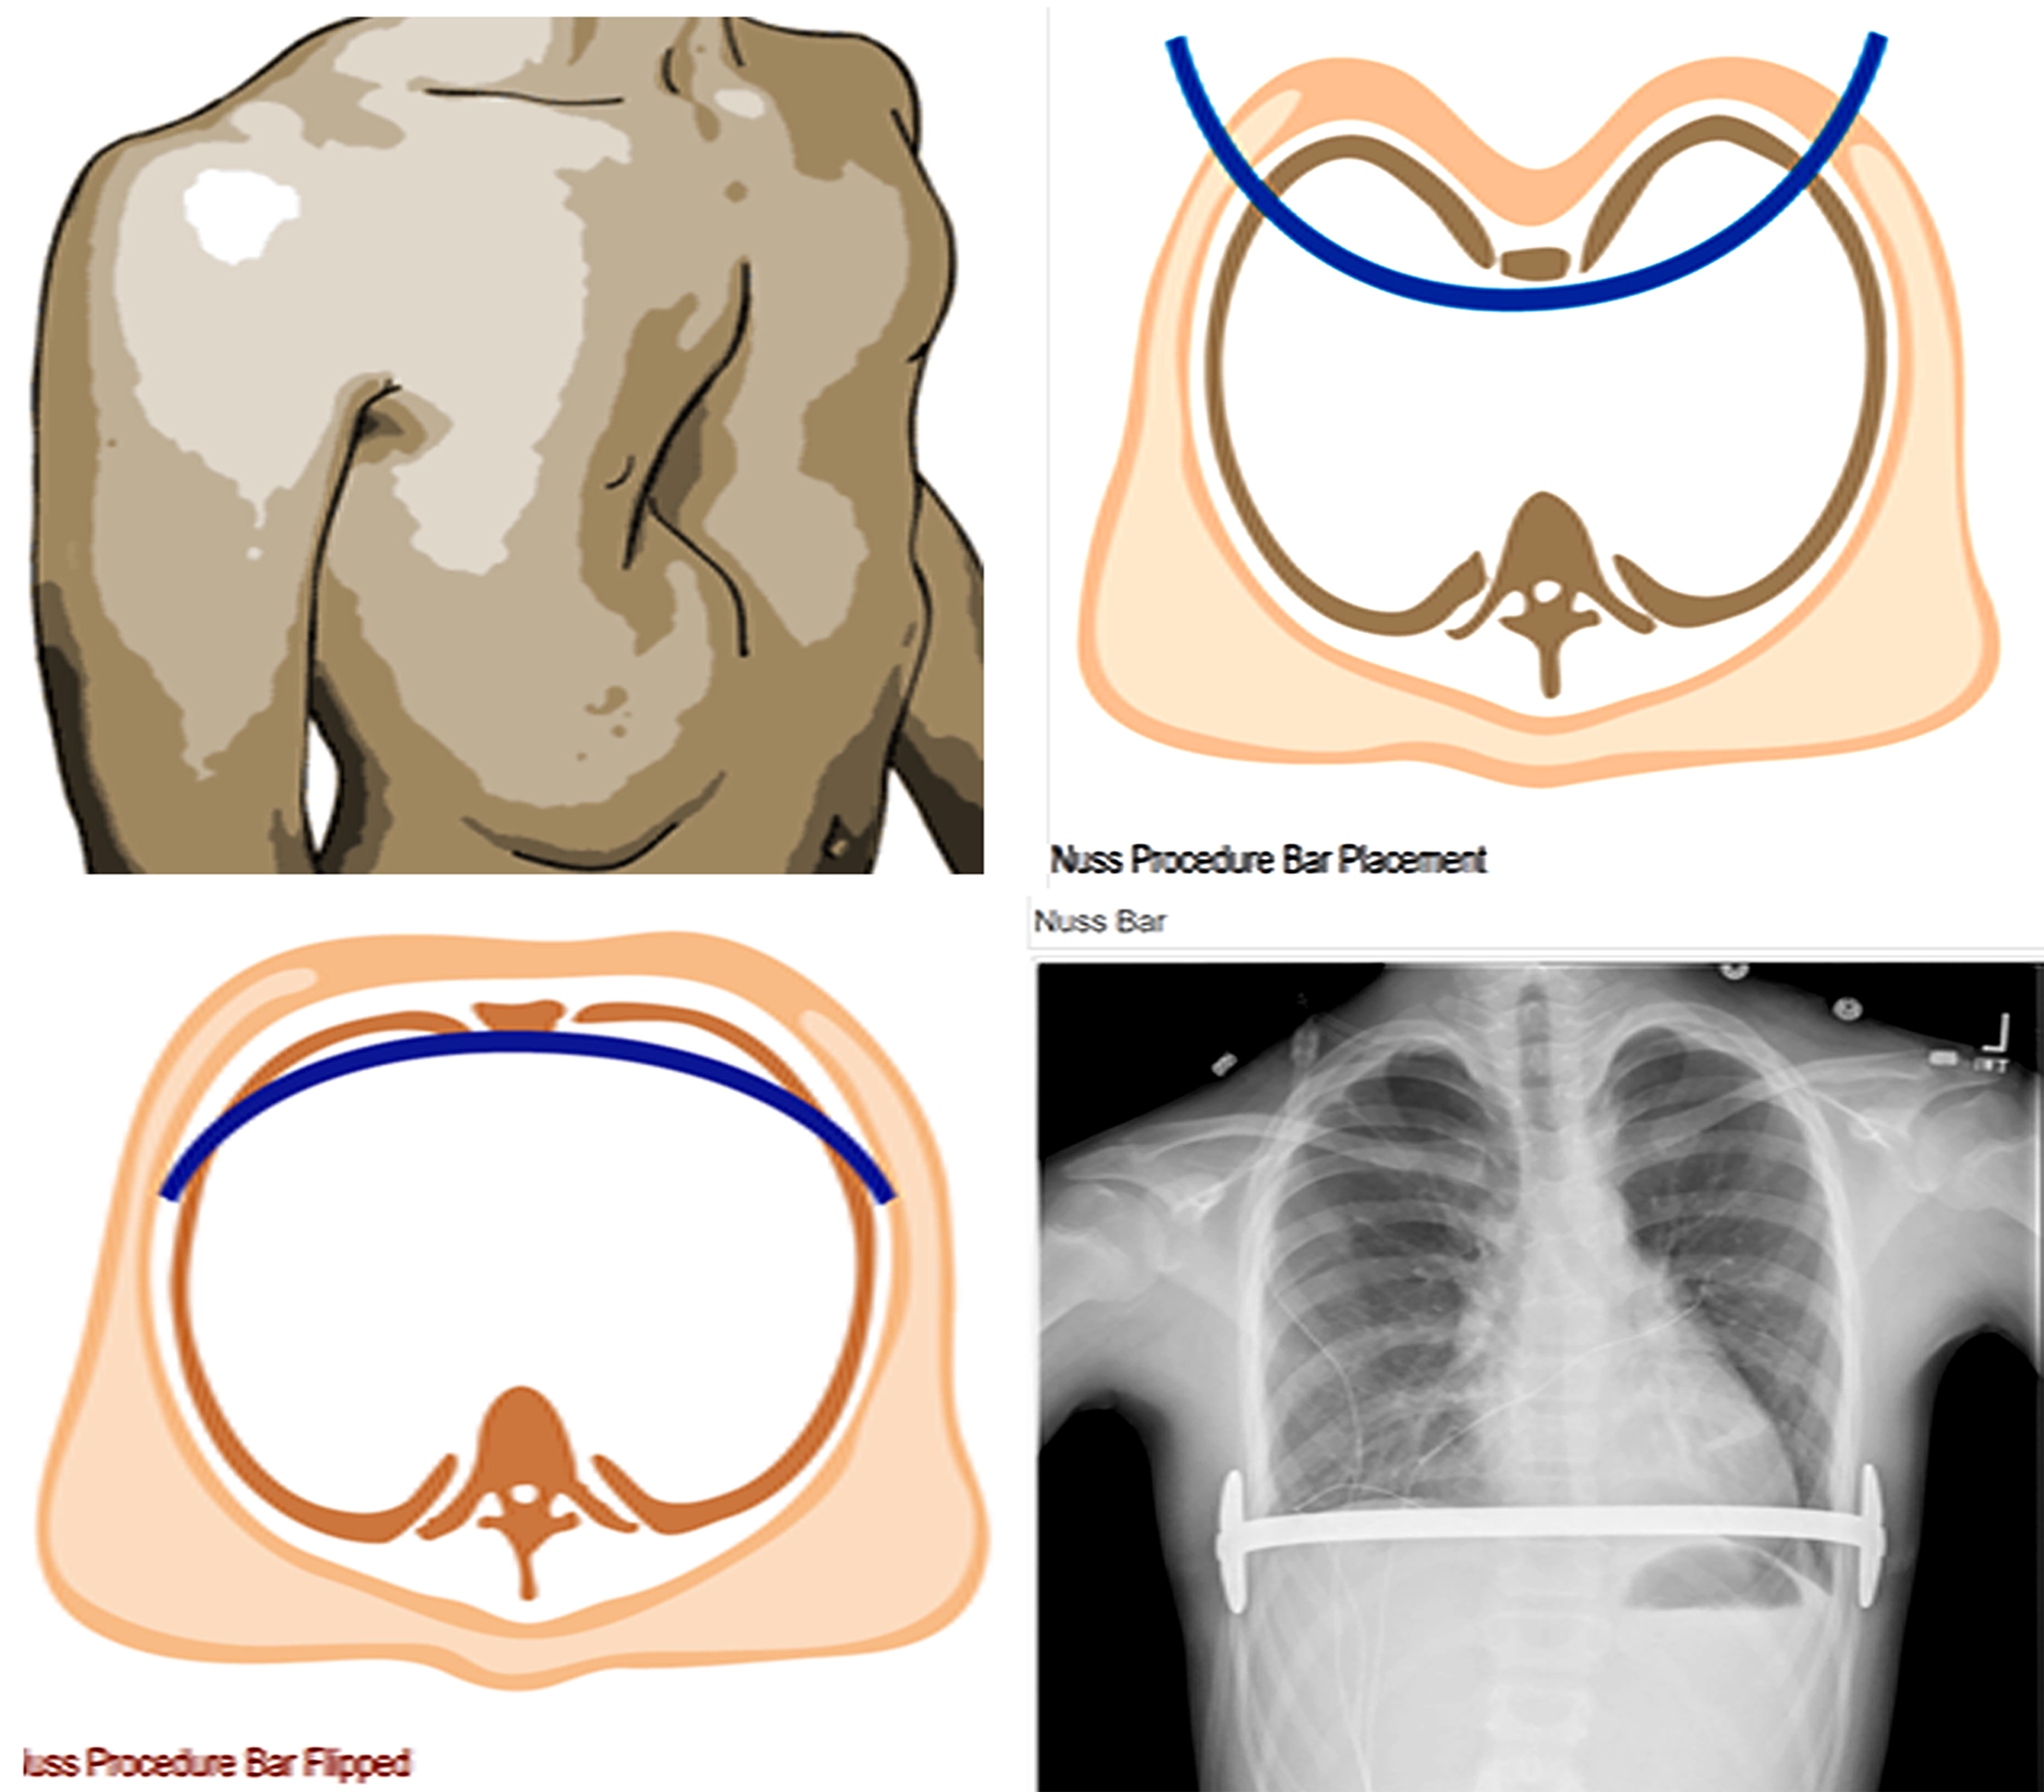

Figure 12 from Anatomical, histologic, and characteristics of What Causes Chest Wall Deformities This article deals with two of the three most common chest deformities: Pectus excavatum (funnel chest) and pectus carinatum. A chest wall deformity is a structural abnormality of the chest that can range from mild to severe. Chest wall deformities are a broad set of congenital diseases that can. Primary rib anomalies can be the cause of chest wall deformities.. What Causes Chest Wall Deformities.

Pectus Deformity Chest What Causes Chest Wall Deformities Chest wall deformities are characterized by abnormal development and appearance of the chest wall. Chest wall deformities impair the rib cage expansion and result in restrictive defect (reduced tlc) to variable degrees primarily caused by reduced chest wall compliance. A chest wall deformity is a structural abnormality of the chest that can range from mild to severe. There are 12. What Causes Chest Wall Deformities.

Chest wall deformities Dr. Rami Hamed Center What Causes Chest Wall Deformities A chest wall deformity is a structural abnormality of the chest that can range from mild to severe. What are chest wall deformities? Primary rib anomalies can be the cause of chest wall deformities. This article deals with two of the three most common chest deformities: Chest wall deformities occur when the cartilage. Chest wall deformities are a broad set. What Causes Chest Wall Deformities.

Chest Wall Deformities Types of chest wall deformities Iranian Surgery What Causes Chest Wall Deformities Chest wall deformities occur when the cartilage. Pectus excavatum (funnel chest) and pectus carinatum. Chest wall deformities are a broad set of congenital diseases that can. This article deals with two of the three most common chest deformities: There are 12 pairs of ribs that connect to the vertebra. Chest wall deformities are conditions that cause physical abnormalities of the. What Causes Chest Wall Deformities.